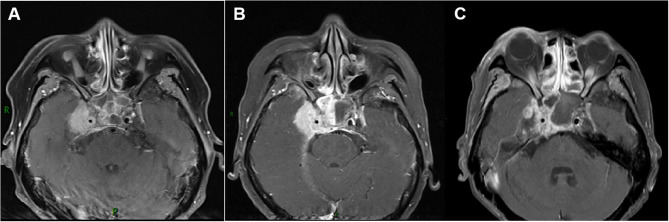

Results: In this study, the efficiency of neoadjuvant immunotherapy combined with chemotherapy was 94.6%, the CR rate was 67.6%, and the efficiency 3 months after IMRT was 100%. The 2-year overall survival (OS), locoregional control (LCR), distant metastasis-free survival (DMFS), and progression-free survival (PFS) rates of the whole group were 97.3%, 94.6%, 97.3% and 91.9%, respectively. Neutropenia was the most common hematological toxicity (100%), and the incidence of grade ≥ 3 neutropenia was 40.5%. Grade 3 anemia and thrombocytopenia did not occur. Additionally, no adverse reactions, such as hypothyroidism, immune pneumonia, or myocarditis, occurred in the whole group. However, the incidences of rash, musculoskeletal pain, and hepatotoxicity were high (45.9%, 54.1% and 37.8%, respectively).